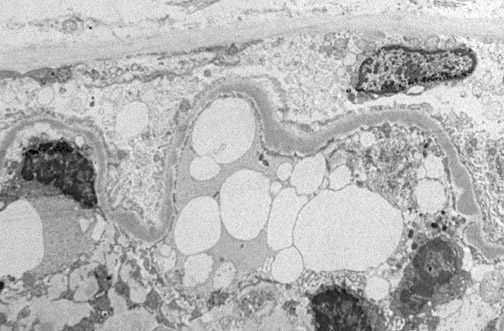

| The electron micrograph above demonstrates dense deposits in the basement membrane typical for MPGN type II. These dark electron dense deposits within the basement membrane often coalesce to form a ribbon-like mass of deposits, as seen in the electron micrograph below. |